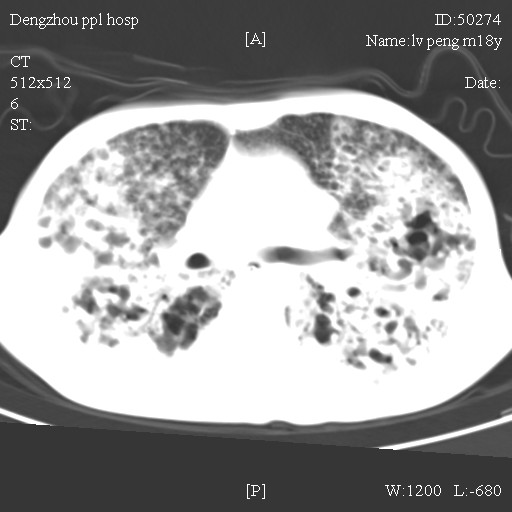

标题: CT10510:男.18岁,咳嗽咳痰两月.(有病理) [打印本页]

标题: CT10510:男.18岁,咳嗽咳痰两月.(有病理)

双肺布满大片状实变及网格状结节影,内参杂大小不等的气囊及空气支气管征,心脏增大。考虑:1 全身结缔组织疾病—系统性红斑狼仓?2 肺泡蛋白沉积症合并感染!

双肺布满大片状实变及网格状结节影,内参杂大小不等的气囊及空气支气管征,双侧胸膜腔少量积液,双下肺近膈面透亮度尚可,病人较年轻,病变较重(不知为什么上胃管?)考虑:1.胶原病肺部改变,2.组织细胞病x。结合实验室检查。

首先考虑组织细胞x病。两肺中上肺野多发囊腔,中下肺野内见多发小结节,并可见肺间质增厚。患者是男性,年龄较小。胶原性病变比较多见的类风湿、系统性红斑狼疮和硬皮病临床和影像均不是很支持,类风湿和系统性红斑狼疮的肺部表现最常见的是胸腔积液,硬皮病可见食管的扩张。

肺内多发斑片状、结节状、融合大片状及网格状影,多发薄壁空腔影,胸膜肥厚,纵隔、气管右移,考虑ⅲ型肺结核,多发空洞,继发肺间质纤维化。

双肺结核并播散.患者以肠梗阻入院,手术为肠结核.术后咳嗽做ct检查.